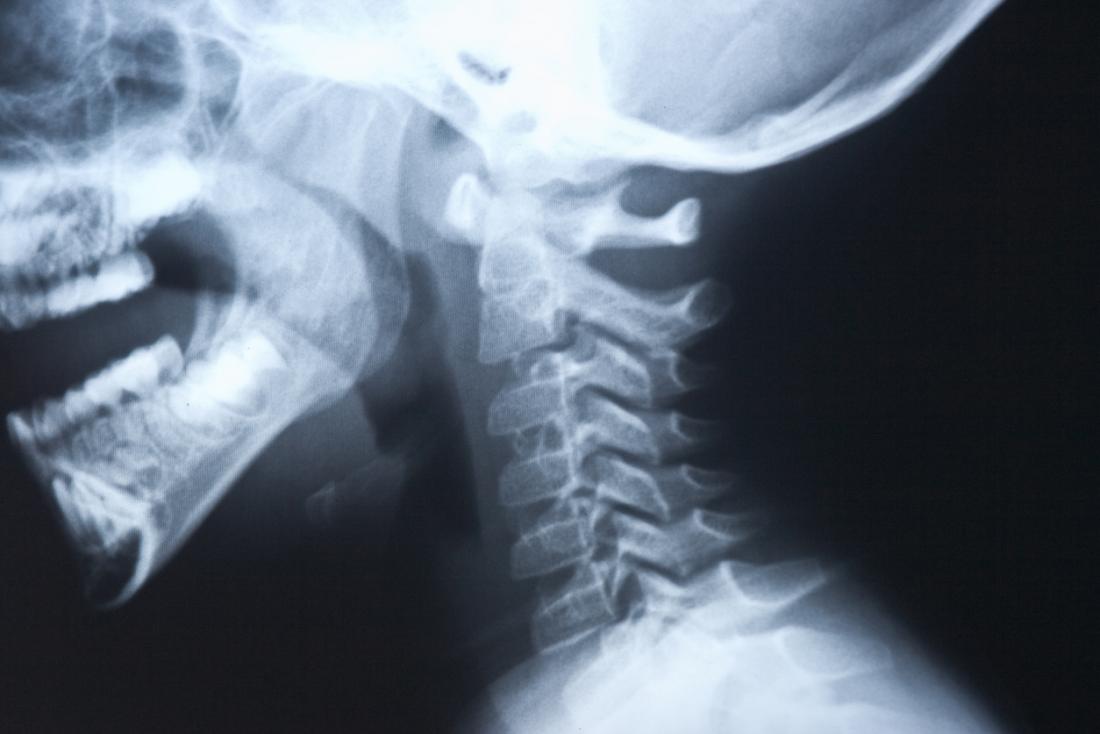

Any condition that causes weakness or damage to the muscles and nerves used for swallowing may lead to dysphagia. This includes diseases such as Parkinson’s, throat, head and neck cancer, side effects from head injuries or stroke, or even just getting old. These conditions inhibit proper neuro-muscular movement and/or control during the swallowing process. As a result, in these patients, food and liquid residue is left over in the throat after swallowing. Such residue can cause a reduction in quality of life, a need to change what and how people eat (in turn causing weight loss, dehydration), and even pneumonia if the residue falls into the airways into the lungs.

Currently, the severity of dysphagia can be assessed visually via a 2D flexible endoscope that is inserted into a patient’s nose and then advanced into their pharynx. However, there is no objective or quantifiable way to measure how much residue is left in a patient’s throat. Clinicians must simply “guess” how much residue is in the throat using their best intuition and experience. This ultimately leads to inconsistent and subjective severity assessments of dysphagia among clinicians, which in turn prevents the meaningful measurement of a patient condition.

Ultimately, such a subjective analysis is an enormous issue for clinical evaluation, documentation, and communication. If only we had someway of quantifying this condition. Imagine Doctor A and B both read from the computer that the patient has 70% severe dysphagia. They are no longer “guessing” because a program is actually calculating severity for them. But with the 2D nature of a standard endoscopic image, such quantification of the 3D anatomy of the hypopharynx is difficult. If only there is a 3D flexible endoscope out there.